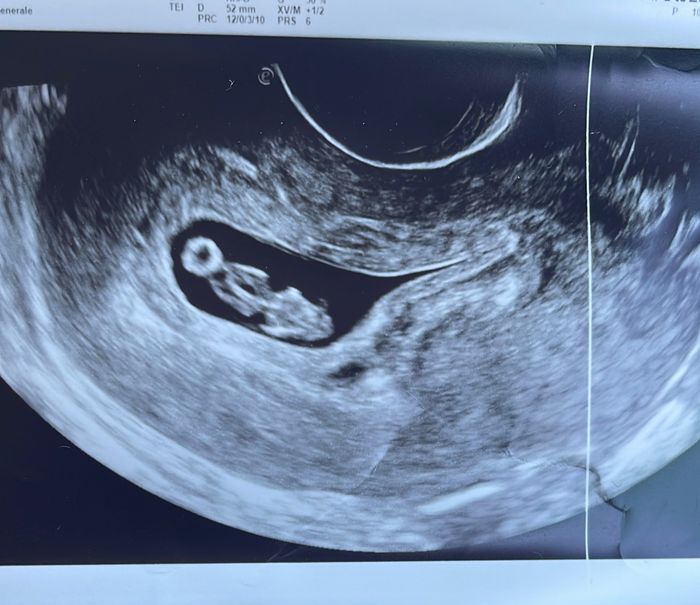

Eco fatta a 7+6 interna.